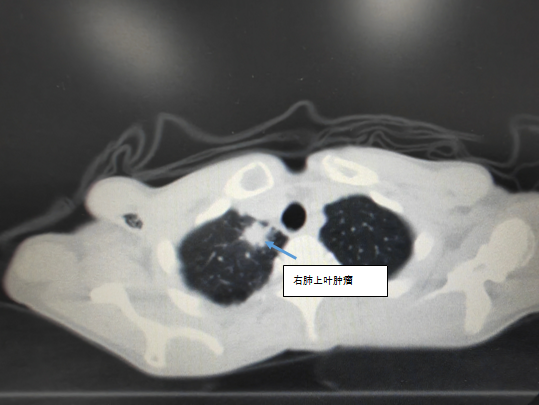

患者为60岁男性,右肺上叶腺癌伴多发转移靶向治疗中,入院前检查右肺上叶病灶较前增大,直径约2.3*1.5cm,为寡进展表现。对于靶向治疗中出现寡进展,指南推荐靶向治疗不变基础上行进展病灶局部治疗。同家属和患者充分沟通后,于2023年7月18日行CT引导下右肺上叶病灶微波消融术,手术过程完成。